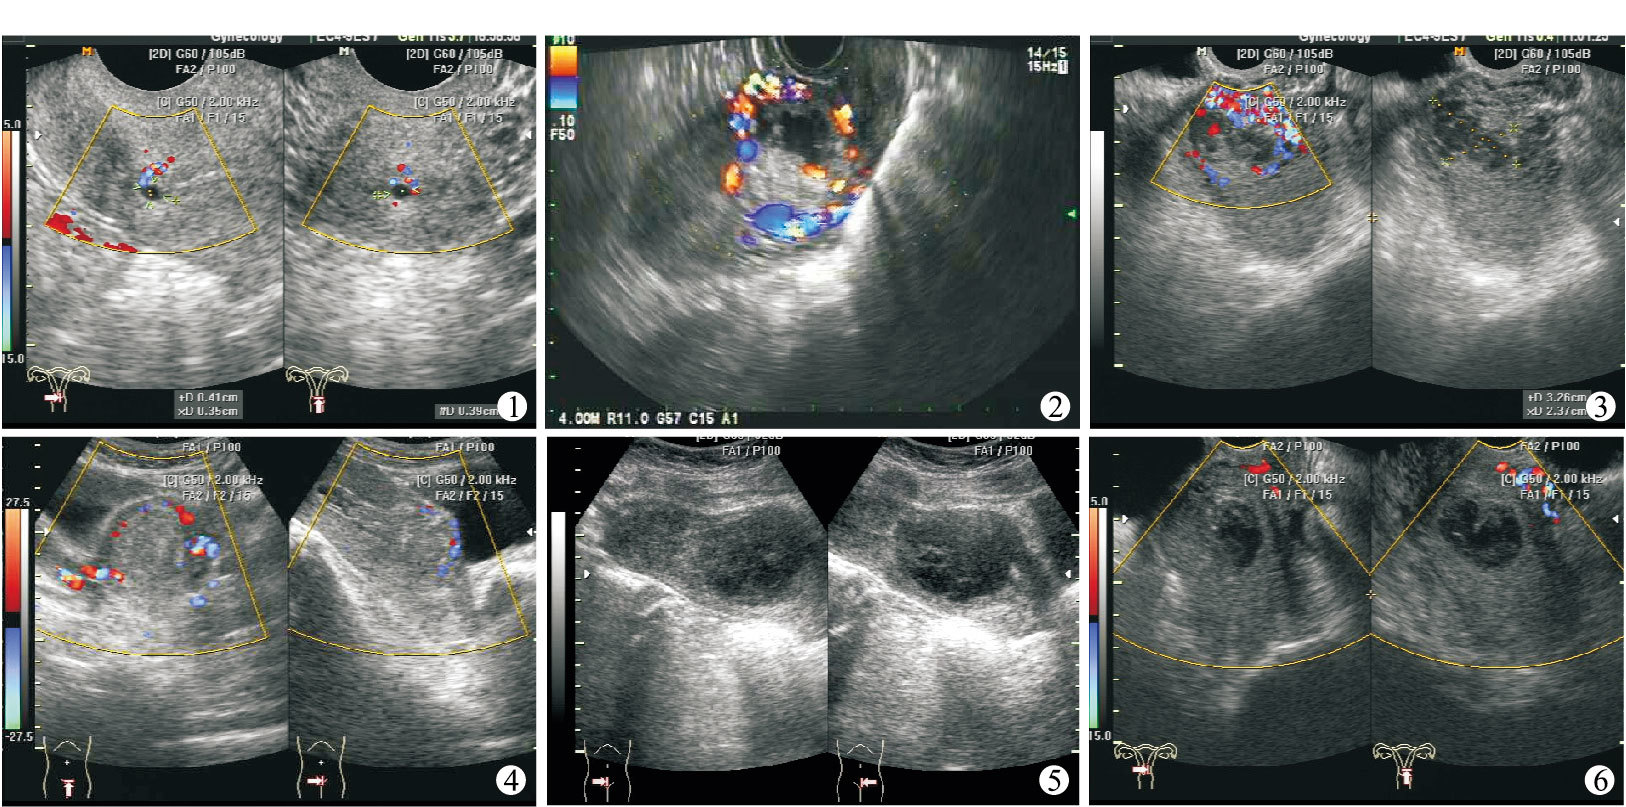

12例患者檢查結果:術前彩色多普勒超聲診斷切口妊娠5例,誤診7例。5例因停經39~43 d,妊娠囊較小完全位于子宮峽部剖宮產切口處的診斷明確(圖 1、2);3例停經45~77 d,因妊娠囊較大向宮腔內生長,而誤診宮內孕行人工流產手術(圖 3~5);2例因陰道流血,切口妊娠流產,切口處顯示為低弱不均質雜亂回聲,誤診為不全流產(圖 6);2例外院人工流產術后陰道流血增多,來我院檢查診斷為切口妊娠。以上患者經子宮動脈栓塞介入治療或其他治療后均得到較好的療效,未發生子宮穿孔或子宮切除。

切口妊娠為異位妊娠的一種,本病病因不明,可能與剖宮產損傷子宮內膜,術后瘢痕組織存在縫隙有關[1]。雖然彩色多普勒超聲聲像圖會因孕期長短、妊娠囊發育情況、陰道有無出血、出血量多少、是否人工流產后等情況而有所不同,但還是有其共同點。以1997年Godin等[2]首次根據剖宮產瘢痕早期妊娠的超聲影像提出的標準:① 子宮內無妊娠囊;② 宮頸管內無妊娠囊;③ 妊娠囊生長在子宮峽部前壁;④ 妊娠囊與膀胱之間肌壁菲薄。即子宮形態改變,峽部偏大,子宮底體部及宮頸管相對較小,峽部回聲異常,峽部肌層隨妊娠囊長大逐漸變薄甚至顯示不清,CDFI顯示子宮瘢痕處妊娠囊周圍有豐富血流,一般呈低速低阻的血流頻譜[3]。不同點:① 典型聲像圖:完全位于切口處的妊娠(圖 1、2),妊娠囊較小,最大徑線<2.0 cm,宮腔上段未見正常妊娠囊,宮內膜增厚回聲均勻,在切口處查見較為完整的妊娠囊,部分可見胚芽及原始心管搏動。子宮峽部增大隨停經時間增加而明顯,縱切時峽部肌層隨妊娠囊長大逐漸變薄,但尚可辨認,CDFI顯示切口處肌層血流信號豐富。此類切口妊娠診斷較為容易。② 不典型聲像圖:妊娠囊部分或少部分著床于峽部切口處,這種情況最易誤診,因停經后大部分妊娠囊向宮腔內生長,僅下緣少部分呈銳角嵌于切口處,妊娠囊內可見胚芽及胎心搏動。隨停經時間延長,妊娠囊可生長較大,甚至到足月,但不可避免的會發生胎盤植入伴前置胎盤,生產時有可能發生大出血甚至切除子宮[4]。超聲醫生在檢查此類切口妊娠時,觀察重點通常在胚胎上而忽略了妊娠囊下緣與切口的關系,也未注意到子宮峽部肌層隨妊娠囊長大逐漸變薄或辨認不清,甚至僅見向外突出的漿膜層回聲。特別是操作時陰道探頭進入較深,又加壓使位于超聲圖像近場的子宮峽部切口處被忽略,不能清楚顯示出妊娠囊下緣與切口的關系,且由于切口處血流信號豐富,如未經腹彩色多普勒超聲補充檢查從而導致誤診。本組3例誤診均屬該種情況,因此凡是剖宮產后再次妊娠的患者超聲檢查時需要超聲醫生有高度的警惕性及切口妊娠的意識,仔細觀察妊娠囊的位置、妊娠囊下緣與切口的關系、切口處有無異常回聲及血流信號是否豐富,避免誤診的發生。③ 超聲誤診宮內早孕而行人工流產手術后聲像圖(圖 3~5):宮腔內及切口處未見妊娠囊回聲,妊娠囊已經部分或大部分被吸出,部分絨毛仍然在切口處,子宮峽部膨隆,呈網格狀或蜂窩樣低弱不均質回聲,邊界不清,縱切肌層顯示不清,僅見菲薄的漿膜層,CDFI顯示網格狀或蜂窩樣低回聲內血流信號異常豐富。④ 切口妊娠流產聲像圖(圖 6):妊娠囊形態改變,峽部及宮腔下段查見不均質低弱回聲團,部分團塊內有不規則無回聲。不均質弱回聲團與峽部切口處關系密切,界限不清,子宮縱切峽部略膨隆,切口處肌層變薄,尚可辨認,CDFI顯示不均質回聲團周邊及切口處血流信號豐富[5]。如果超聲醫生經驗欠缺,無切口妊娠的意識,切口妊娠流產也易誤診為不全流產。